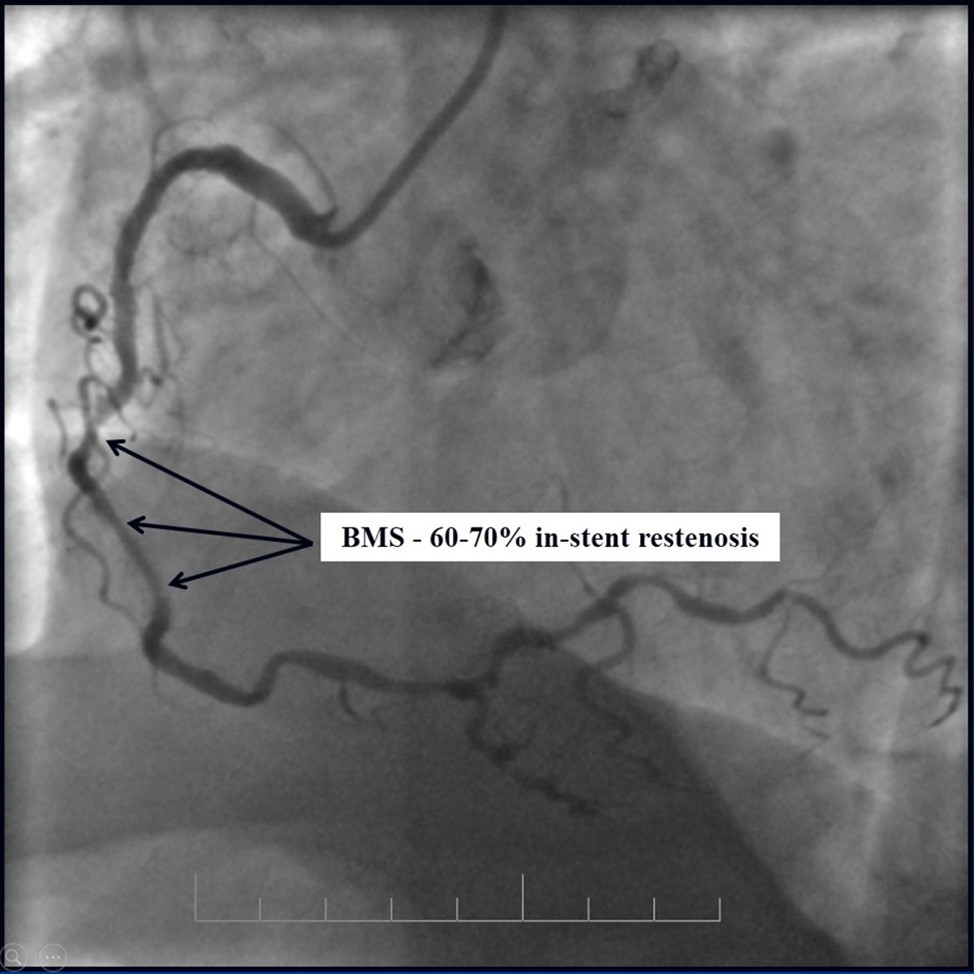

Due to financial problems the second stage was performed after 3 months (during this time the patient solved his financial problems). CAG revealed patent stents in LAD (Figure 7), and 60-70% restenosis by BMS in RCA (Figure 8). In-stent restenosis was treated by plain old balloon angioplasty (POBA), the optimal result was obtained (Figure 9). After LMCA quadrifurcation balloon predilation, 2.5×26 mm DES (Resolute Integrity, Medtronic) was implanted in the IMA, using a modified balloon mini-crush technique. The stent was minimally protruded in the LMCA and its edge was crushed by preloaded MB balloon. Next 2.5×30 mm DES (Resolute Integrity, Medtronic) was implanted in OM1 through the CX (first marginal and circumflex arteries in this particular case have the same ostium). The stent was protruded in the LMCA as in conventional modified balloon crush stenting technique, after stent deployment, its balloon was pulled back and overinflated, then protruded stent was crushed by preloaded MB balloon (Figure 10). 3.5×15 mm DES was implanted in the LMCA so that distal part of the stent covered ostial and proximal segments of the LAD. Sequential post-dilatations were performed using a kissing balloon technique (1. LMCA-LAD-IMA,2. LMCA-LAD-CX-1OM). After post-dilatations, through the stent implanted in CX-OM1, coronary wire and smaller diameter balloon (2.0 mm) were advanced in direction of the CX mid-segment and by balloon dilatation stent’s strut was opened (provisional stenting technique for CX). Finally, the proximal optimization technique was performed in the LMCA using a 3.5 mm diameter non-compliant balloon (Figure 11). The final angiographic image was good, the intervention ended without complications (Figure 11, Figure 12). We could not confirm the result with IVUS or OCT due to several technical and financial problems (not covered by insurance). 1 month after PCI, at regular checkout, the ejection fraction was 48%, the functional class of the Congestive Heart Failure decreased from class II-III to class I and the patient complaints have been disappeared.

Figure 8.RCA, 60-70% in-stent restenosis in BMS

Subsequent coronary angiography eight months after the last PCI revealed patent stents with mild, non-significant restenosis in DES and 50-60% in-stent restenosis in BMS (Figure 13, Figure 14).

Figure 13.Subsequent CAG eight months after last PCI; A - Patent stents with mild, non-significant restenosis in left coronary artery; B - 50-60% in-stent restenosis in RCA.